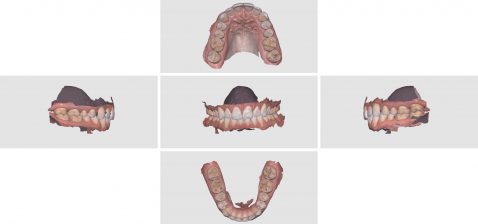

Virtual Extractions for Overdenture with Shining 3D

June 11, 2020upper denture duplicated with shining 3d. only needed the occlusal and buccal surfaces as the case is for a lower overdenture over immediate extractions, on healed implants. went ahead and […]